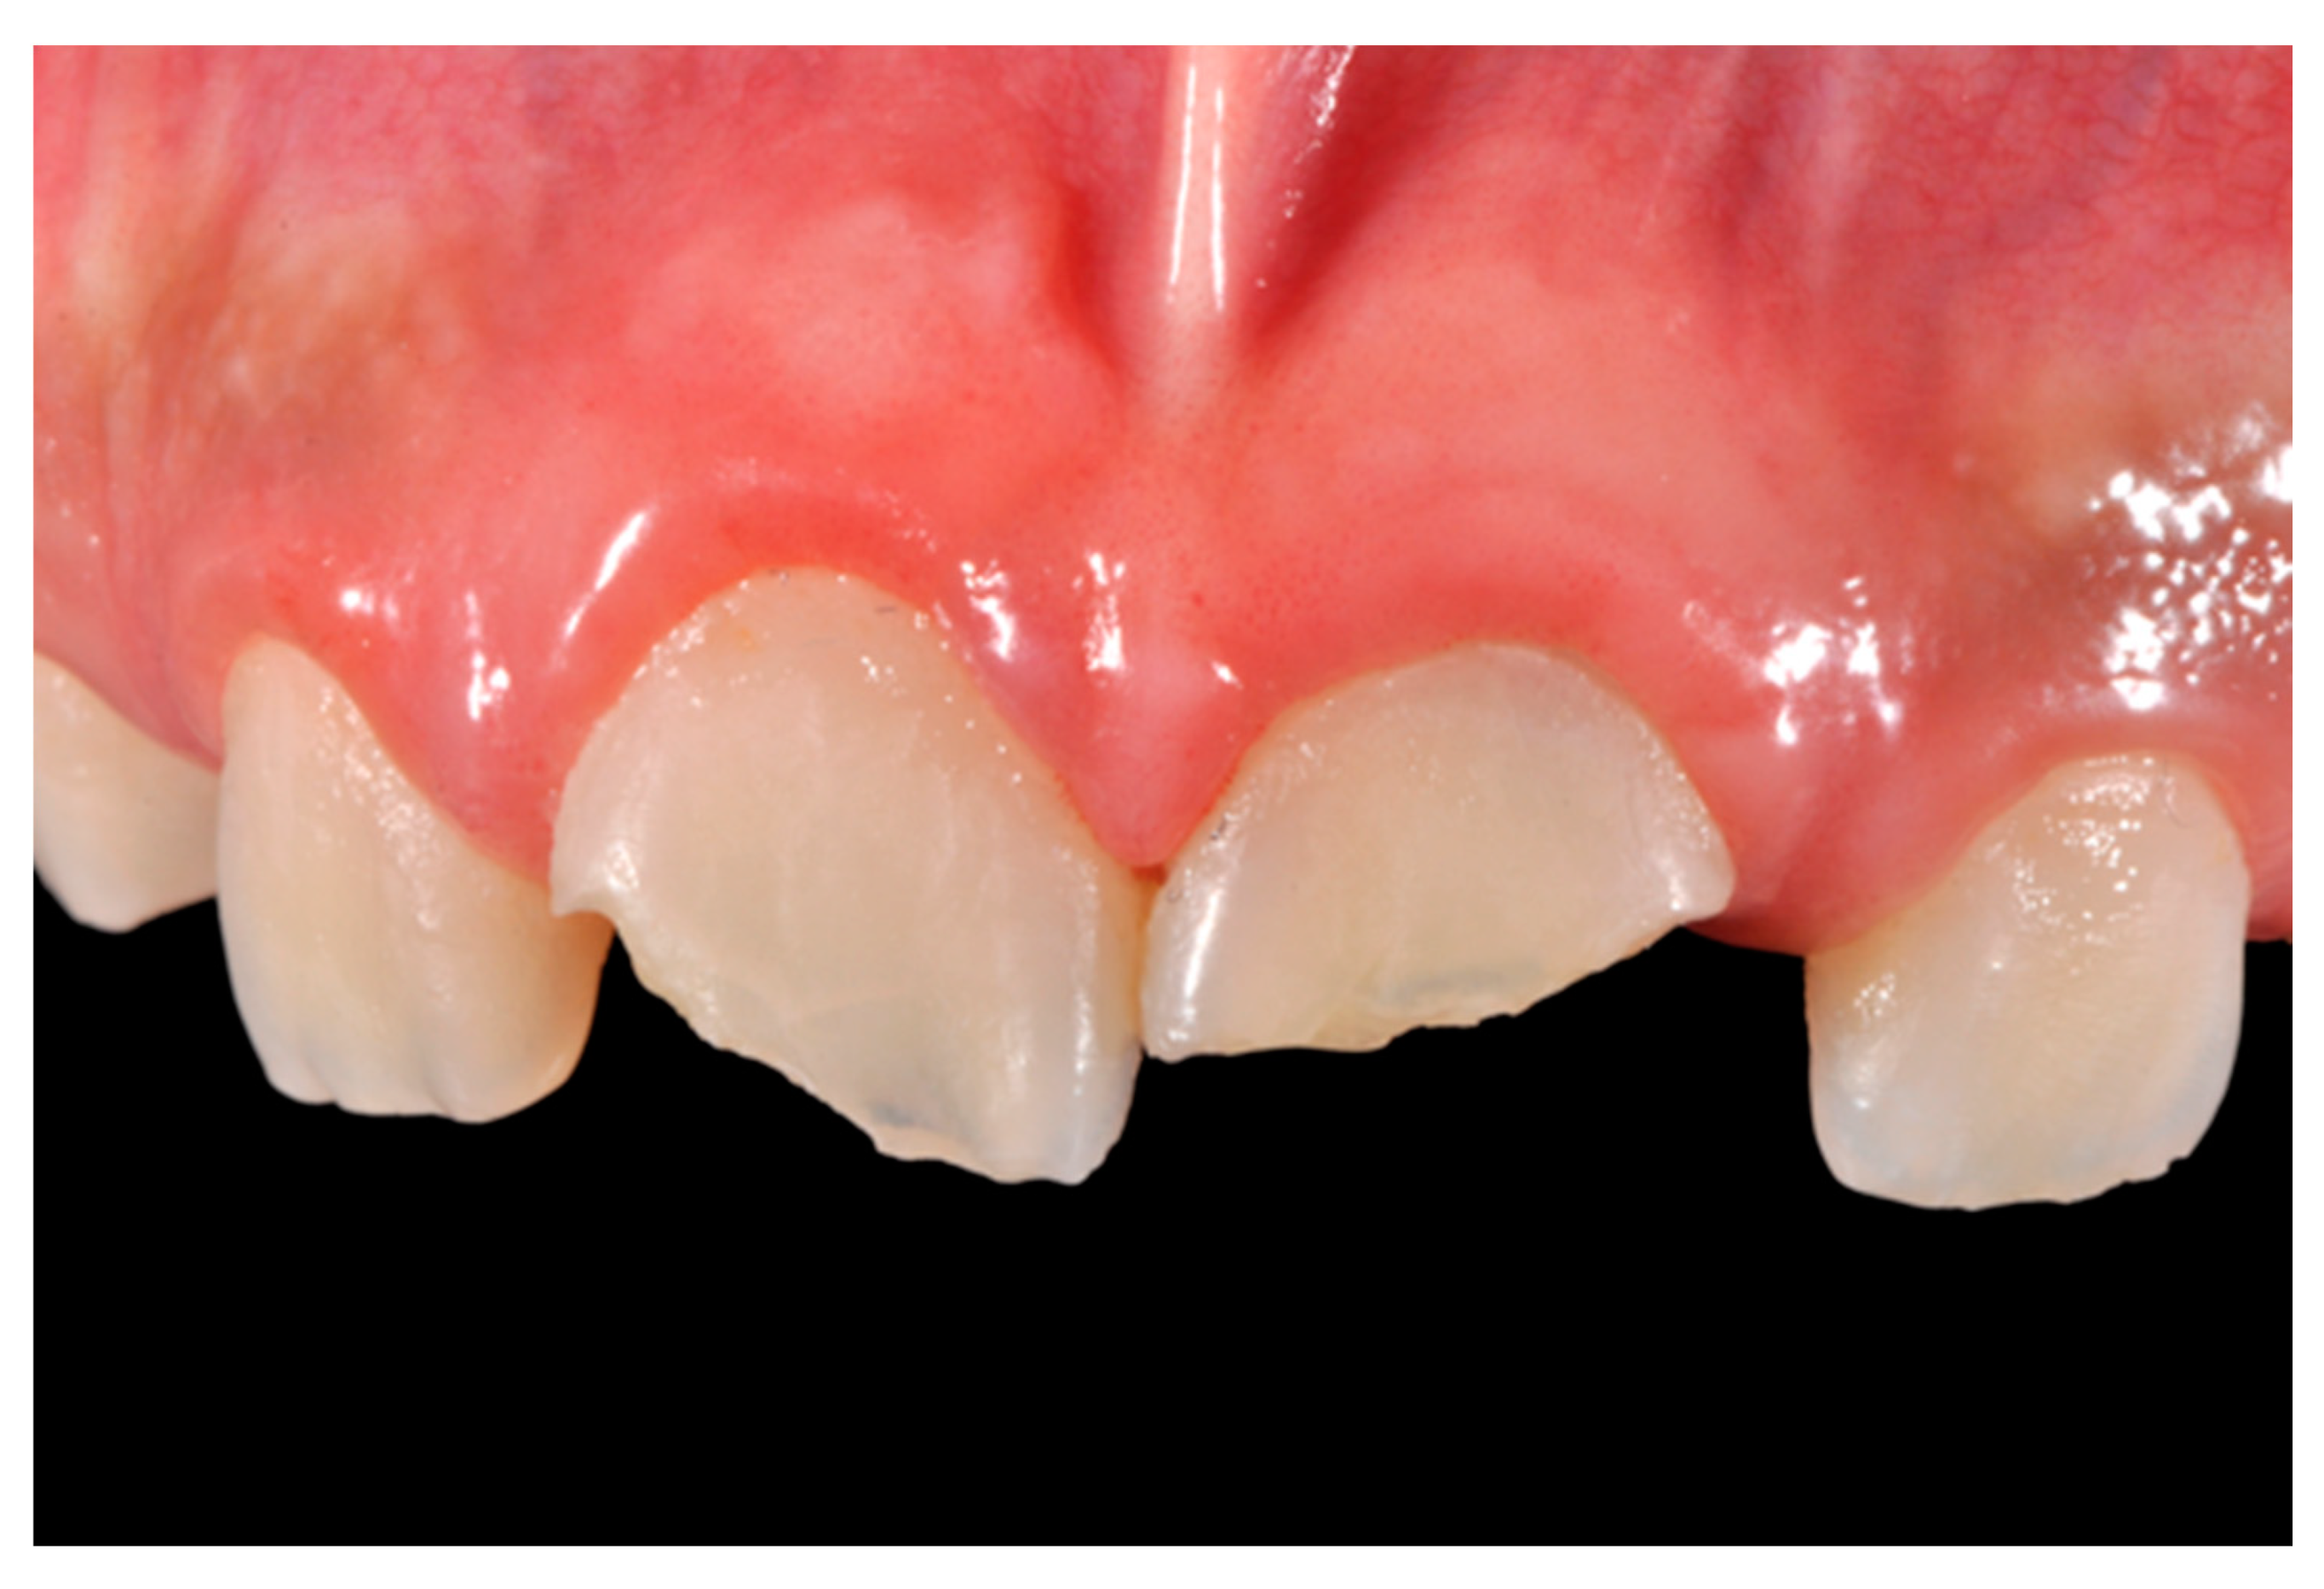

Dentistry Journal Free Full Text The Pre Finishing Approach In Direct Anterior Restorations A Case Series Html